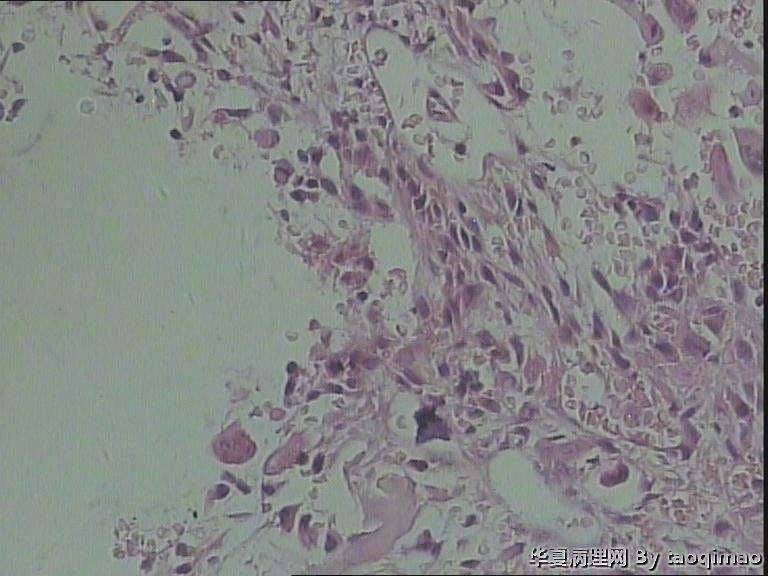

• 肋骨肿物,求助图1

这是比较容易取下来的部分,肋骨内部的肿瘤还在制片中

患者女,31岁,胸部CT第八肋骨肿瘤,肿物在肋骨内突出骨外膜,大小2.3X1.5.切面灰白质韧

这是一部分容易取下来的肿瘤,其余部分还在脱钙中

骨母细胞瘤。矿化不均要除外骨母细胞型骨肉瘤,虽然肿块小了点。还是找找核分裂,看看X线的好。

那就是骨样骨瘤。